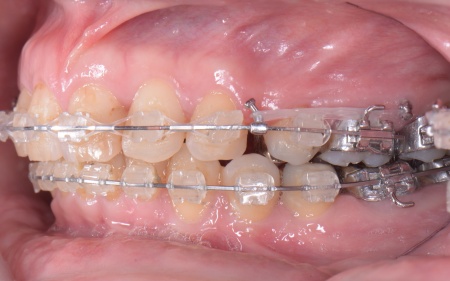

患者様の場合、骨格的な上顎前突が噛み合わせを乱している主な原因であることから、矯正治療では前歯を後方へ大きく動かすためのスペースを確保する必要があります。 そのため、今回は以下2つの方法を提案しました。 ①抜歯後、アンカースクリューを用いたワイヤー矯正 メリット:骨格的な上顎前突に対応しやすく、前歯を大きく後方へ動かすことができる ②取り外し可能な装置を使用するマウスピース矯正 メリット:装置が透明で目立ちにくく、取り外しができる 以上のメリットとデメリットを丁寧にお伝えしたところ、患者様は①のアンカースクリューを用いたワイヤー矯正を選択されました。 まず、上顎の左右奥歯を抜き、前歯を後方に動かすためのスペースを確保します。 治療の結果、前歯が正しく噛み合うようになり、横顔のバランスも整いました。 矯正治療終了後は、歯が元の場所に戻らないよう上下前歯に保定装置(リテーナー)を装着し、治療を終了しています。 |